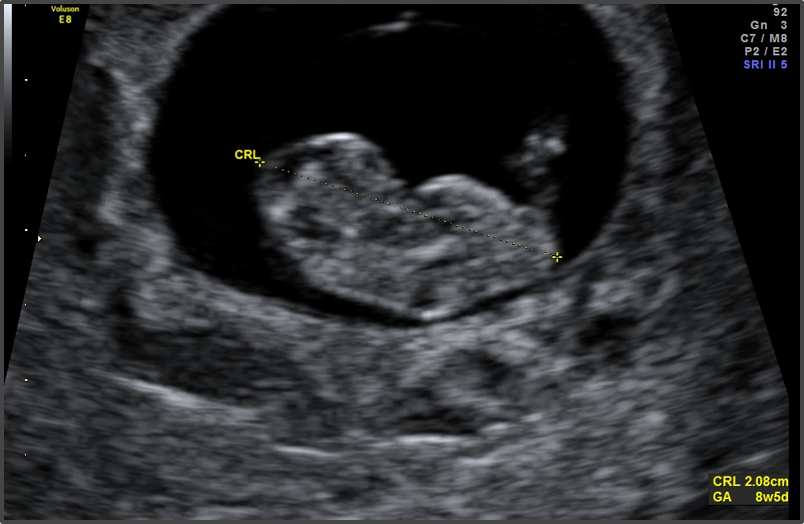

Baby is the size of Raspberry

Approx Baby Weight: 1.5g

Approx Baby Size: 1.6 cm